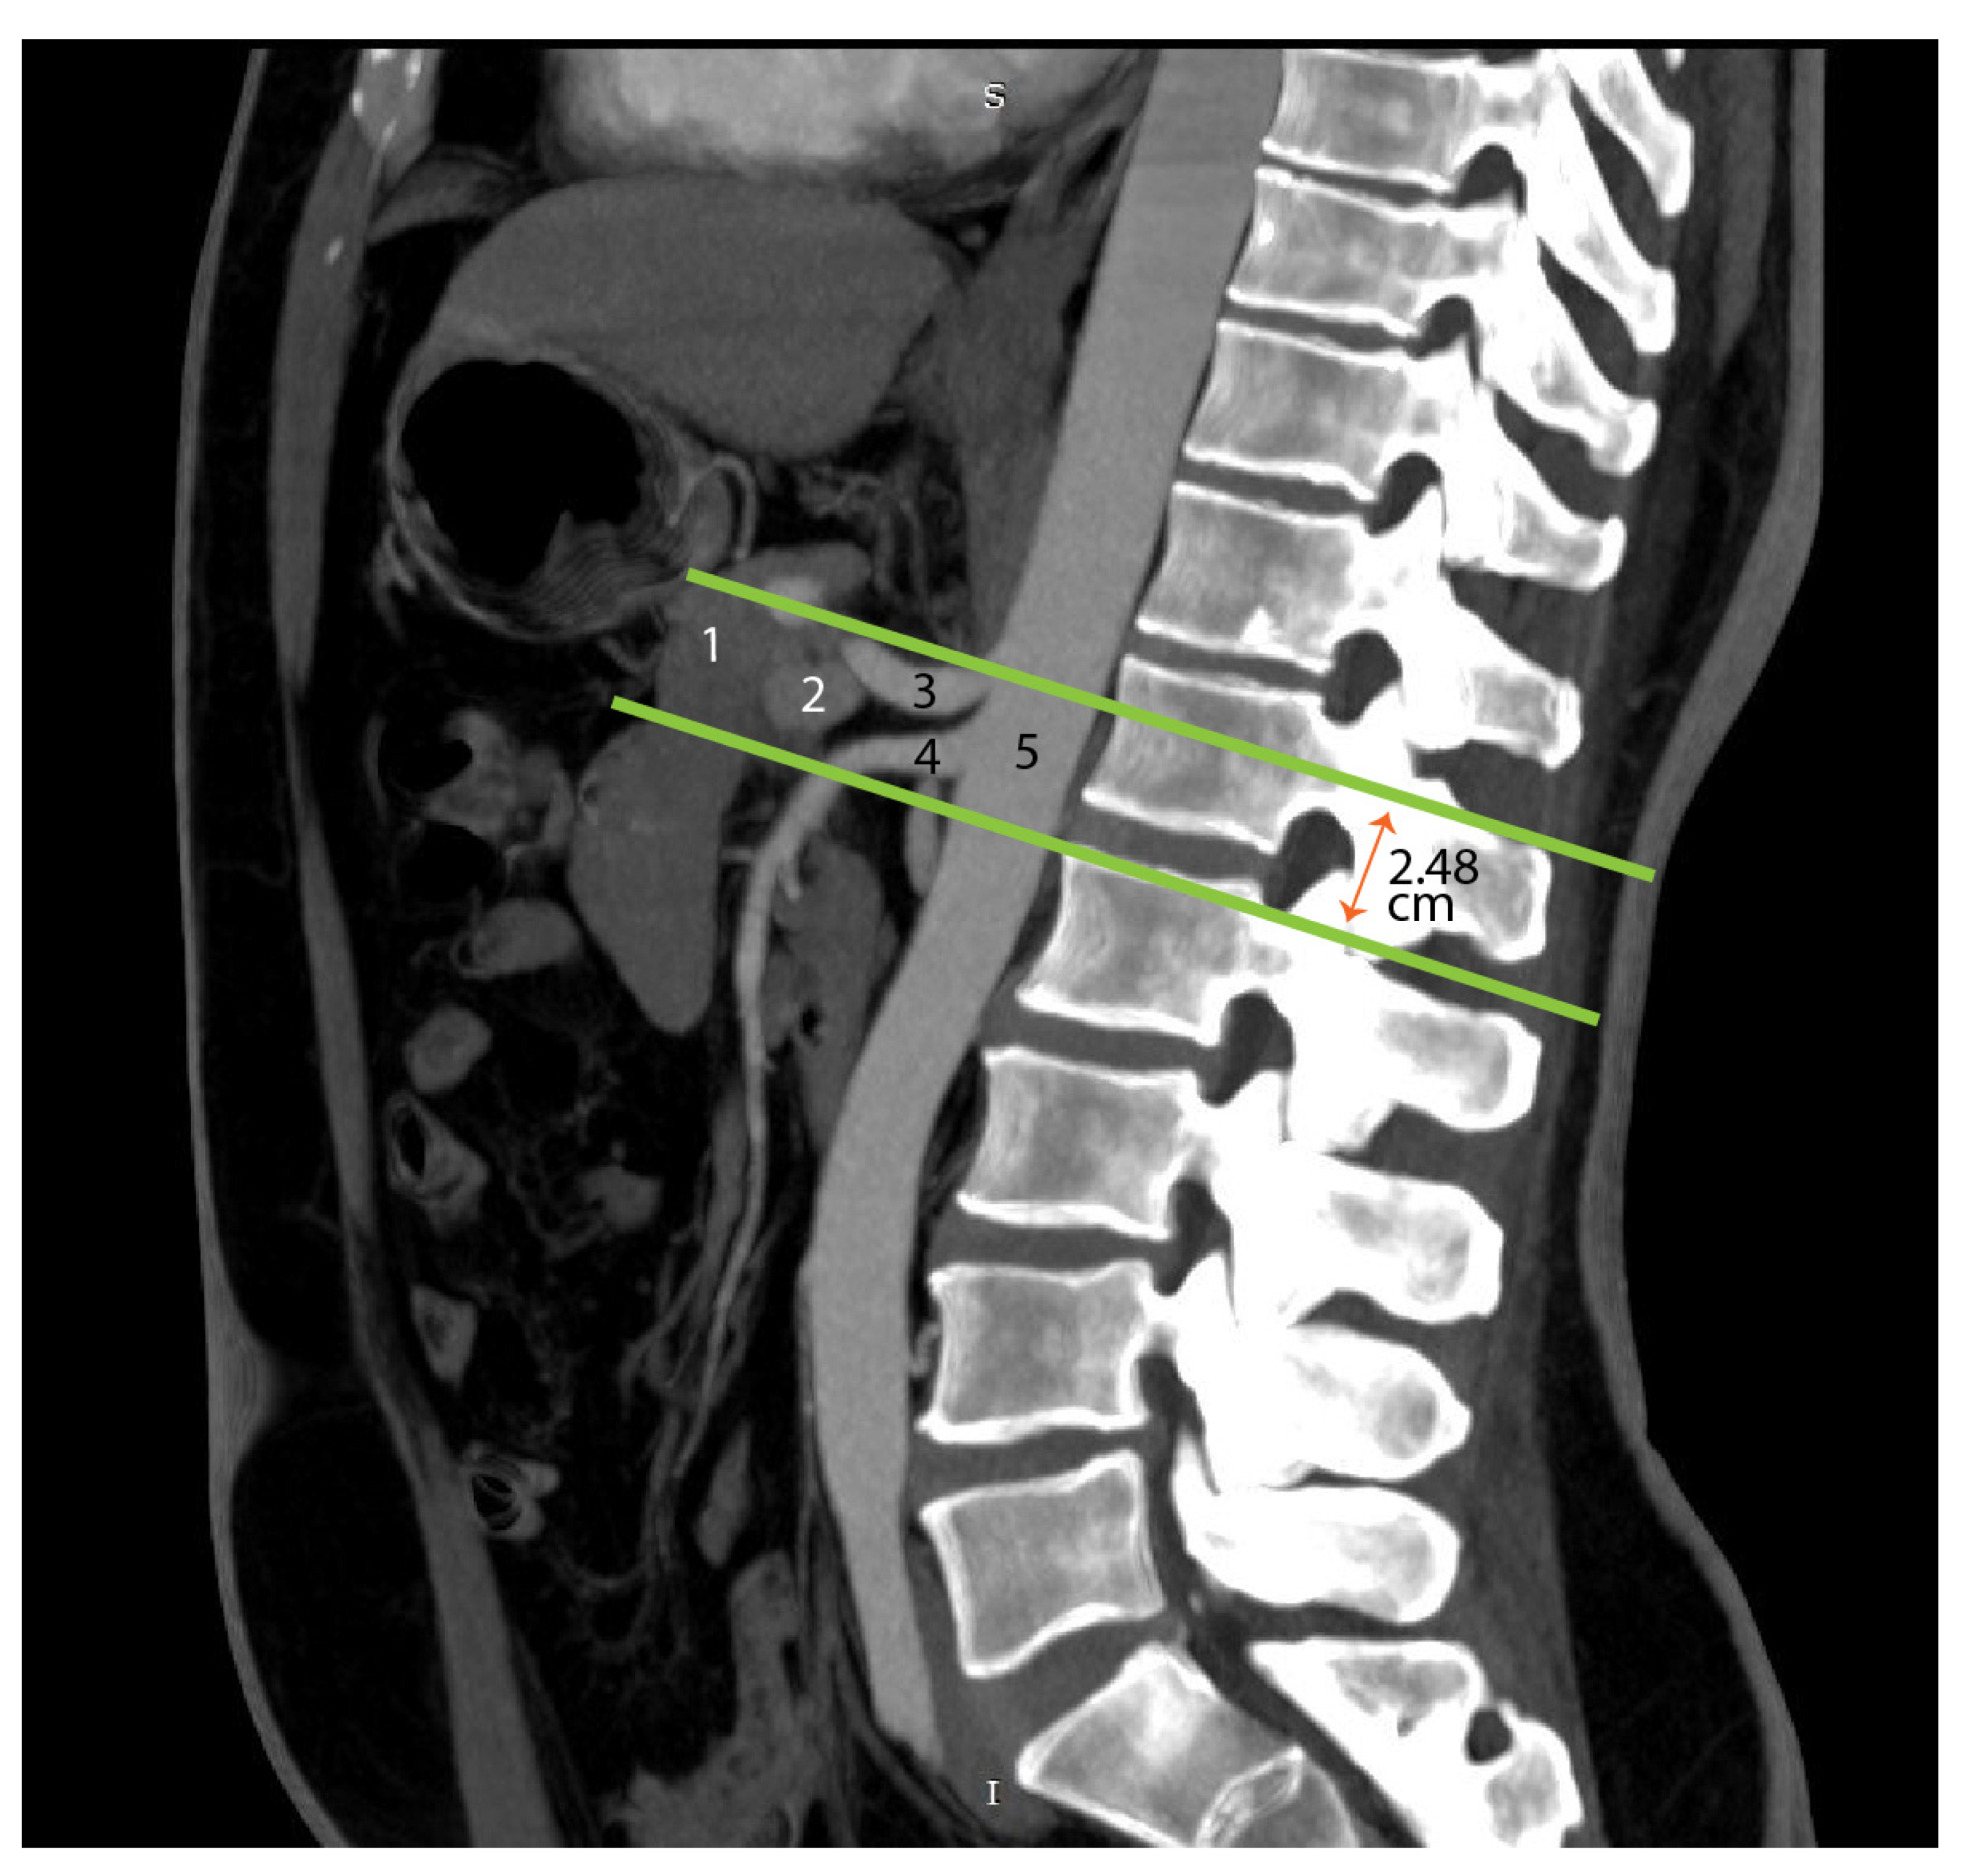

4.5. Advances in Imaging